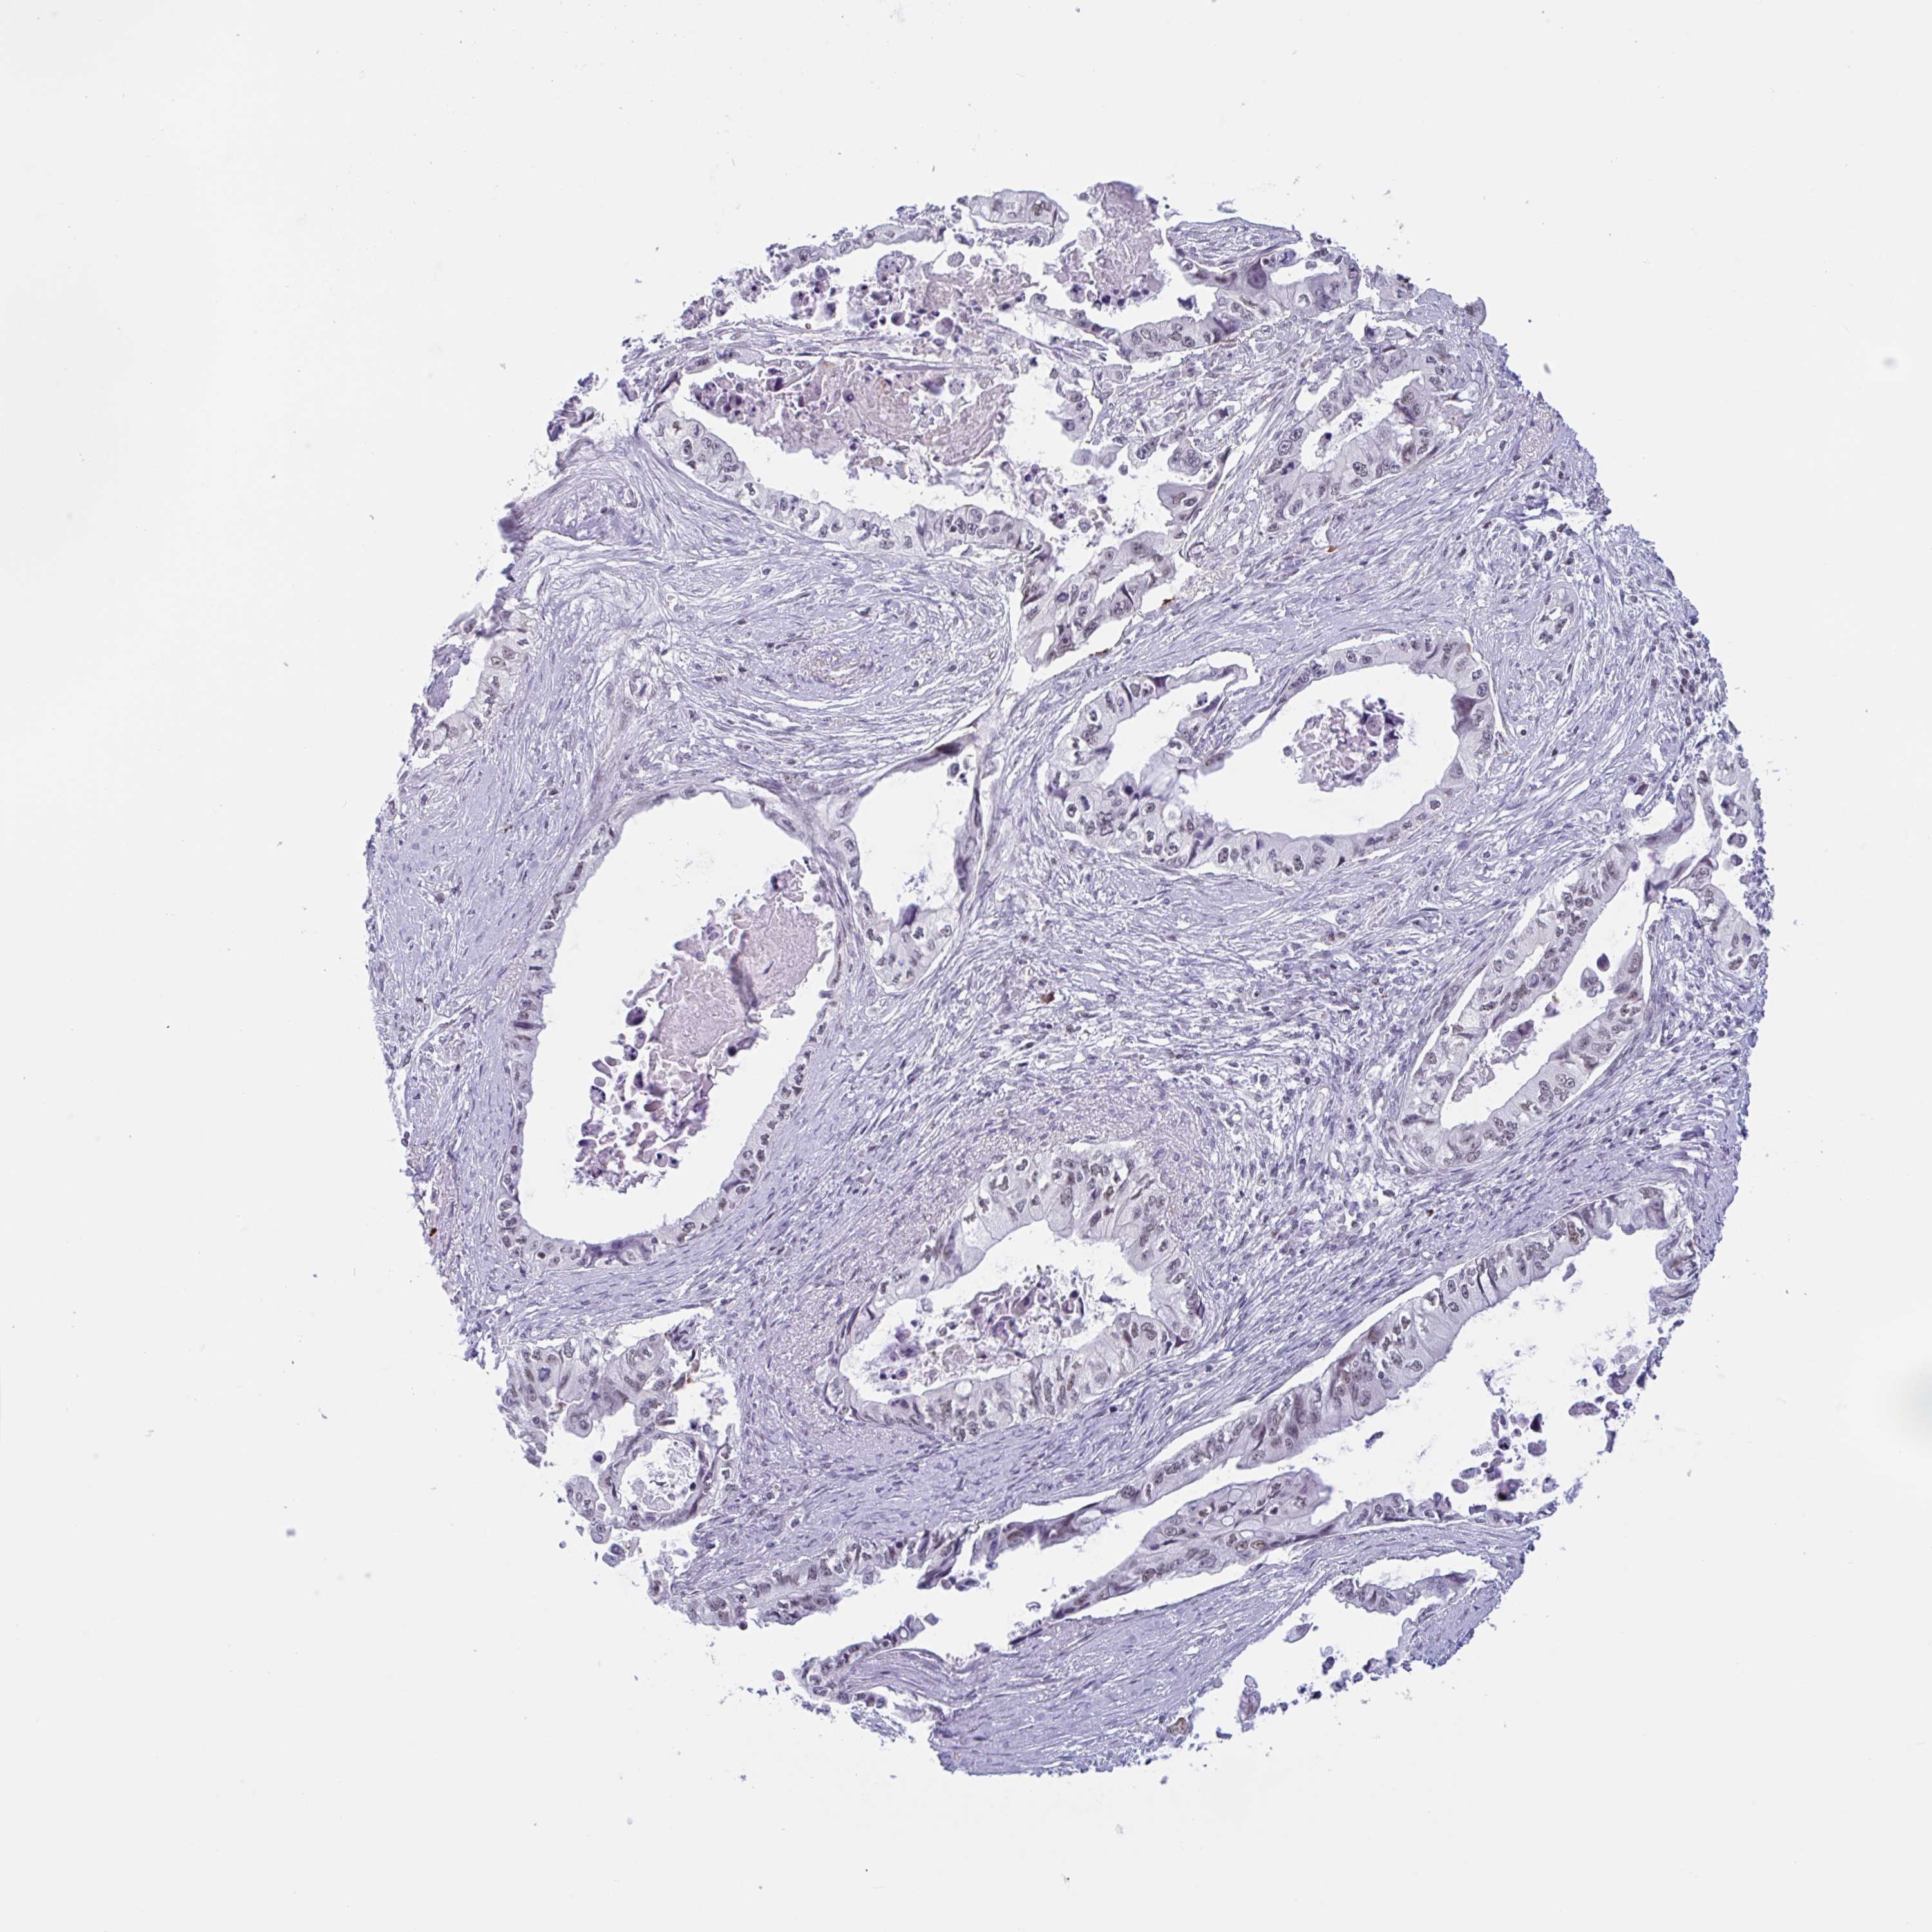

PANCREATIC CANCER - Protein expressioni

A mouse-over function shows sample information and annotation data. Click on an image to view it in a full screen mode. Samples can be filtered based on level of antibody staining by selecting one or several of the following categories: high, medium, low and not detected. The assay and annotation is described here.

Note that samples used for immunohistochemistry by the Human Protein Atlas do not correspond to samples in the TCGA dataset.

Antibody stainingi

Antibody staining in the annotated cell types in the current human tissue is reported as not detected, low, medium, or high, based on conventional immunohistochemistry profiling in selected tissues. This score is based on the combination of the staining intensity and fraction of stained cells.

Each image is clickable and will lead to virtual microscopy that enables deeper exploration of all samples and also displays staining intensity scores, fraction scores and subcellular localization as well as patient and tissue information for each sample.

Antibody HPA021602

Antibody HPA048823

Antibody CAB000668

Antibody CAB016678

Adenocarcinoma, NOS